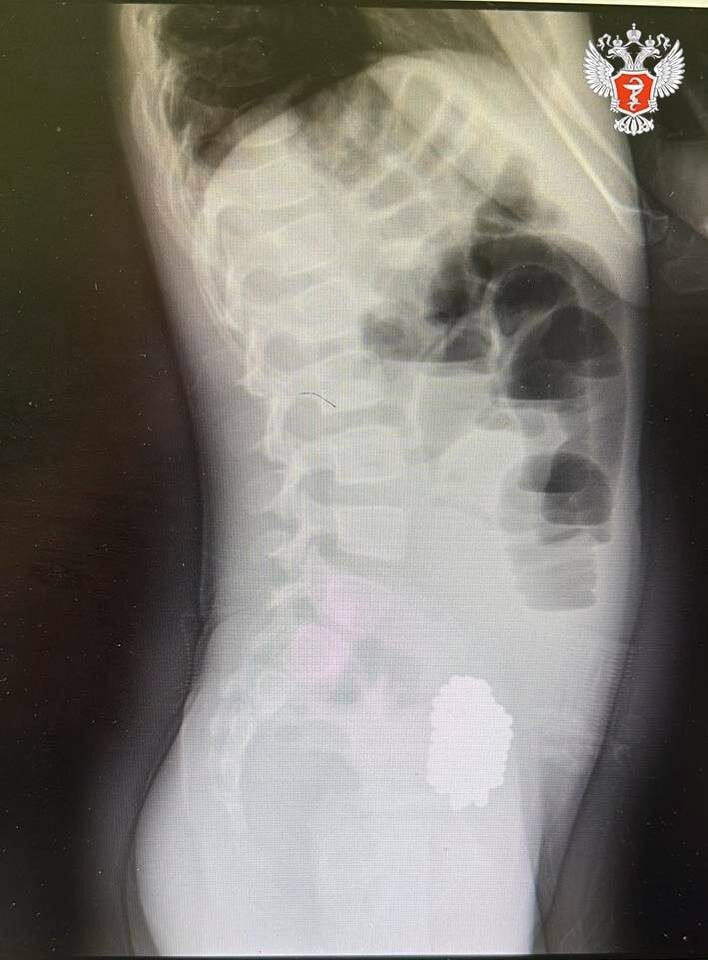

В ходе обследования врачи выявили кишечную непроходимость, вызванную инородным телом. Рентген показал массивный конгломерат из 134 магнитных шариков, которые сдавливали стенки кишечника.